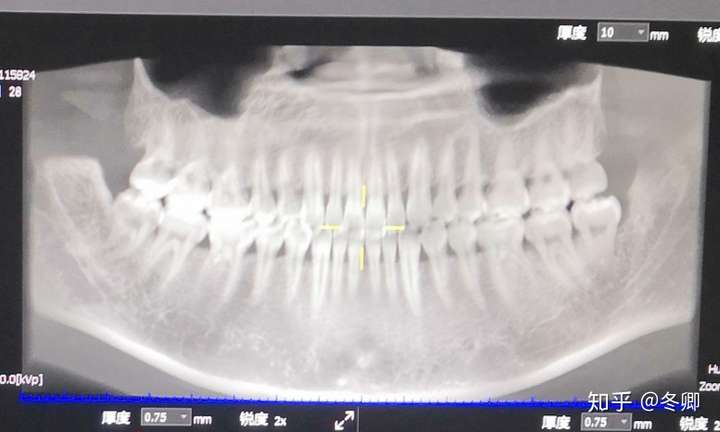

贴牙片,牙片图片

之前有点蛀牙拍的牙片.

贴牙片,昨天去洁牙.医生说要好好清理智齿~目前还没蛀牙

本组最厉害的牙片

先贴个牙片

牙痛,长了智齿,拍了个牙片——拔牙

全景牙片

智齿牙片